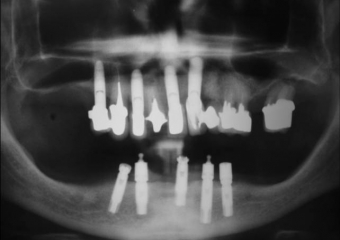

Próteses fixas em porcelana sobre implantes